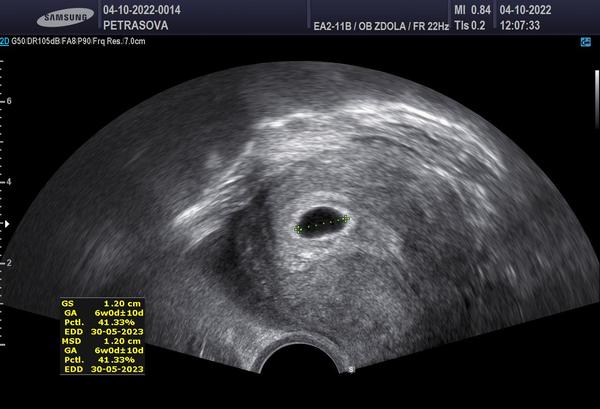

Holky vyzna se v tom někdo ? Já tedy ne 😁 poslední Ms jsem měla 19.srpna , cykly jsem měla delší cca 35 ,31 dní ovulace byla kolem toho 19 dne .. první pozitivní test jsem měla 18.zari večer .. na první kontrole jsem byla teď v úterý . Těhotenství potvrzeno , srdíčko ještě nebylo vidět ..podle ultrazvuku jsem byla v úterý 6+0. Plus minus deset dní jestli jsem to správně pochopila 😃 mám se stresovat nebo je to vpohode.. Doktror se mě ptal ,jak mám dlouhé cykly a říkal ,že to tedy odpovídá .jen mě trošku znervózňuje to srdíčko. Na další ultrazvuk jdu 25.10